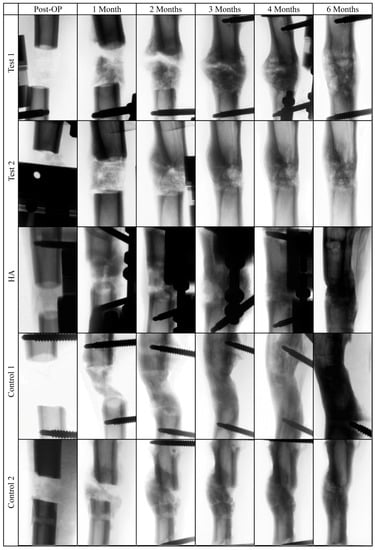

2.6. X-Ray Analysis

The images of the bone defect area revealed comparable radiographic signs of profound new bone formation and bridging of the defect site after six months (Figure 4). Increased callus formation could be observed in the test group after two, three, and four months, which completely disappeared after five months.

Figure 4.

Representative invers radiograph images of the tibial bone defect area after surgery and after one, two, three, four, and six months.